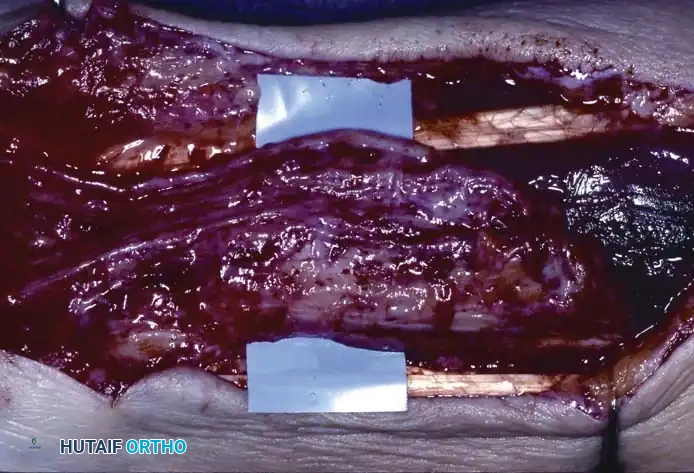

Careful separation of the ganglion from the surrounding extensor tendon sheaths.

- Stalk Excision: Using a combination of sharp and blunt dissection, mobilize the ganglion in its entirety. Trace the stalk down to its capsular origin at the dorsal scapholunate ligament. Excise the cyst along with a 1-cm margin of the dorsal capsule. Do not excise the substance of the scapholunate interosseous ligament itself, as this will cause carpal instability.

Excision of the ganglion stalk along with a generous margin of the dorsal joint capsule.